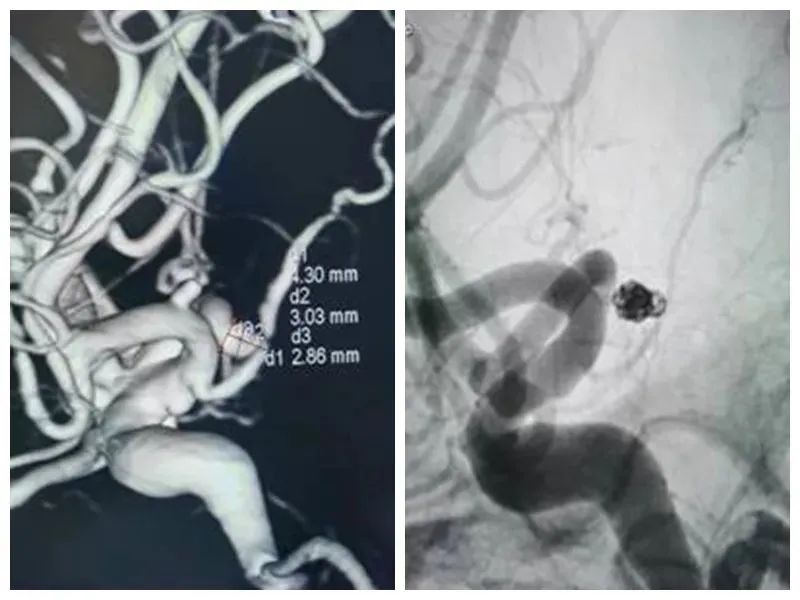

數字減影血管造影(DSA)

內二科早在2007年便開展急性腦梗超早期溶栓治療並取得可喜成果,不少生(shēng)命垂危的病人經積極溶栓治療後得到較好的治療效果,對急性腦出血的處理上也有獨到的經驗。內二科在2018年成立了卒中中心,由多學科聯合組成的腦血管病診斷治療快(kuài)速反應小組,為急性(xìng)腦血(xuè)管疾病患者(zhě)開通(tōng)了綠(lǜ)色通道,為腦(nǎo)血管疾病患者治療爭取寶貴時間。因此內(nèi)二科的工作得到社會各界的認(rèn)可,於2019年12月順利通過國家級卒中中心評審。特別(bié)是醫院在(zài)2020年底引進(jìn)數字減影血管造影X線機,目前內二科已常規開展腦(nǎo)血管造影,腦梗死取栓,顱內動脈瘤填塞,腦血管支架植入等手術。

數字減影(yǐng)血管造影(DSA)、1.5T雙引擎磁共振、320排CT、數字減影血(xuè)管造(zào)影X線機、常規腦電圖、24小(xiǎo)時動態(tài)腦電圖、肌電圖、誘發電位(wèi),經顱多(duō)普勒(TCD)、腦(nǎo)脊(jǐ)液檢查、基因檢測(cè)等。